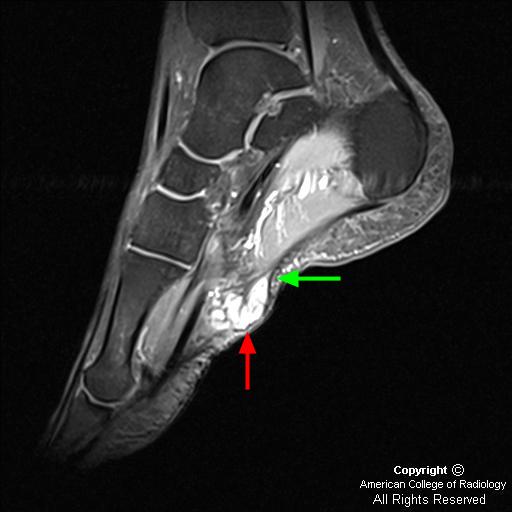

Плантарный фиброматоз (синдром Леддерхозе, описан им в 1897 г) в отличие от пальмарного фиброматоза редко сопровождается сгибательиой контрактурой. Поражает обычно медиальный отдел подошвы стопы (плантарный апоневроз) и имеет вид узелков, с течением времени достигающих 4—5 см в поперечнике. Узлы обычно плотные, множественные, связаны с фасциальными образованиями. Микроскопически новообразованная ткань богата фибробластоподобиыми клетками.

Подошвенный фиброматоз

Плантарный фиброматоз